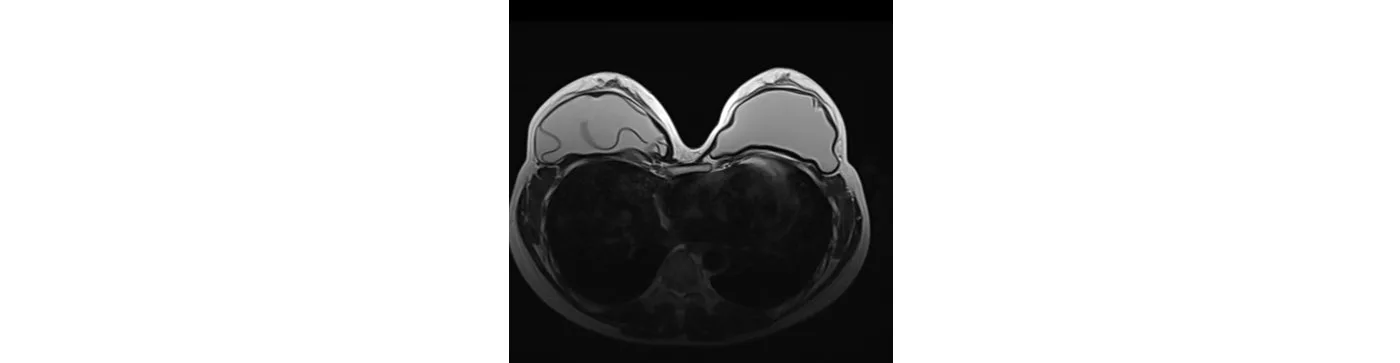

Người bệnh nữ 36 tuổi, sau đặt túi ngực 5 năm, đi khám định kì, chụp cộng hưởng từ túi ngực phát hiện rách trong bao túi ngực bên phải.